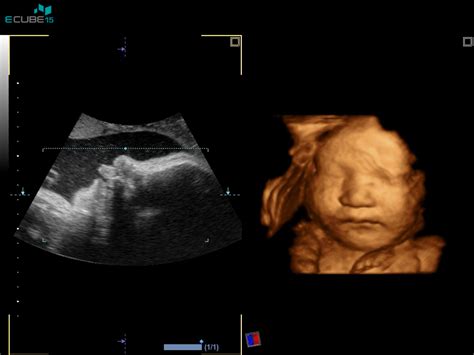

Fetalna biometrija: ključno orodje za spremljanje rasti

Fetalna biometrija je bistvena sestavina predporodne oskrbe, ki vključuje natančno merjenje velikosti in rasti ploda med nosečnostjo z uporabo ultrazvoka. Ta metoda zagotavlja dragocene vpoglede v razvoj otroka in pomaga zdravstvenim delavcem oceniti, ali plod raste zdravo.

Ključne meritve v fetalni biometriji:

- Dolžina krone (CRL - Crown-Rump Length): Ta meritev, ki se običajno opravi v prvem trimesečju, meri dolžino otroka od vrha glave do dna zadnjice. Uporablja se za oceno gestacijske starosti.

- Biparietalni premer (BPD - Biparietal Diameter): Meri razdaljo med obema stranema otrokove glave na ravni talamusa.

- Obseg glave (HC - Head Circumference): Določa obseg otrokove glave.

- Obseg trebuha (AC - Abdominal Circumference): Ta meritev pomaga oceniti rast ploda in delovanje posteljice.

- Dolžina stegnenice (FL - Femur Length): Meri dolžino stegnenice (stegenske kosti) za oceno razvoja okostja.

Rezultati fetalne biometrije se primerjajo s standardiziranimi krivuljami rasti glede na gestacijsko starost. Odstopanja od normale lahko kažejo na intrauterino omejitev rasti (IUGR), kjer plod ne raste pravilno, ali na makrosomijo, kjer je plod večji od pričakovanega za svojo gestacijsko starost. Slednje je lahko povezano z zdravstvenimi stanjmi, kot je gestacijski diabetes.

Fetalna biometrija je varna in neinvazivna metoda, ki pa ne služi za napoved točnega datuma poroda. Pogostost ultrazvočnih pregledov je odvisna od poteka nosečnosti in morebitnih tveganj.